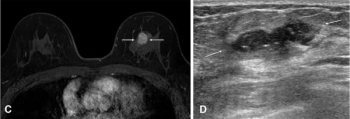

Preoperative breast MRI had no impact upon recurrence-free survival and overall survival for women with HER-2 positive, hormone receptor-negative breast cancer, according to a multivariable analysis of a new study involving nearly 1,100 women.